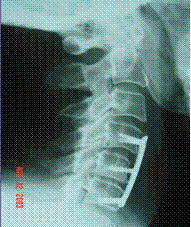

NHAC used in spine fusion operation

(Photos Provided by Professor Cui Fu-Zhai)